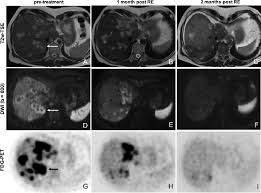

What Are The Symptoms Of Metastatic Breast Cancer In The Liver / Images In A 53 Year Old Woman With Metastatic Breast Cancer In The Download Scientific Diagram : Metastasized, or metastatic breast cancer has spread beyond the breast to distant body sites.

What Are The Symptoms Of Metastatic Breast Cancer In The Liver / Images In A 53 Year Old Woman With Metastatic Breast Cancer In The Download Scientific Diagram : Metastasized, or metastatic breast cancer has spread beyond the breast to distant body sites.. Further workup will then often. The symptoms that present with metastatic breast cancer usually depend on where the cancer has spread. It does not treat the cancer itself. Most of the time, metastatic breast cancer affects the bones, lungs, brain, or liver. Changes in treatment are made as the cancer grows or spreads to new places in your body.

Metastatic breast cancer is also classified as stage 4 breast cancer. Metastatic cancer is cancer that spreads from its site of origin to another part of the body. The symptoms and signs that people with metastatic breast cancer may experience depend on where and liver metastasis symptoms. Fibrocystic condition causes noncancerous changes in the breast that can make. Metastatic breast cancer (also called stage iv) is breast cancer that has spread to another part of the body, most commonly the liver, brain, bones, or lungs.

Secondary Breast Cancer In The Liver from i.ytimg.com Fibrocystic condition causes noncancerous changes in the breast that can make. It's also referred to as advanced breast cancer. Metastatic breast cancer is essentially stage iv breast cancer. Treatment aims to control and slow down the spread of the cancer, relieve symptoms and give you the best quality of life for this is because secondary breast cancer in the liver can cause the liver to become enlarged. Other nonspecific systemic symptoms of metastatic breast cancer can include fatigue, weight loss. The most common areas of breast cancer metastasis are the bones, brain, lungs, and liver. Memorial sloan kettering doctors specializing in liver metastases are experts at figuring out what's going on and helping you feel better. With metastatic breast cancer, the goal of treatment is to shrink or weaken the cancer, manage your symptoms and side effects and prevent the cancer from spreading further.

Metastatic breast cancer, also referred to as metastases, advanced breast cancer, secondary tumors, secondaries or stage iv breast cancer, is a stage of breast cancer where the breast cancer cells have spread to distant sites beyond the axillary lymph nodes.